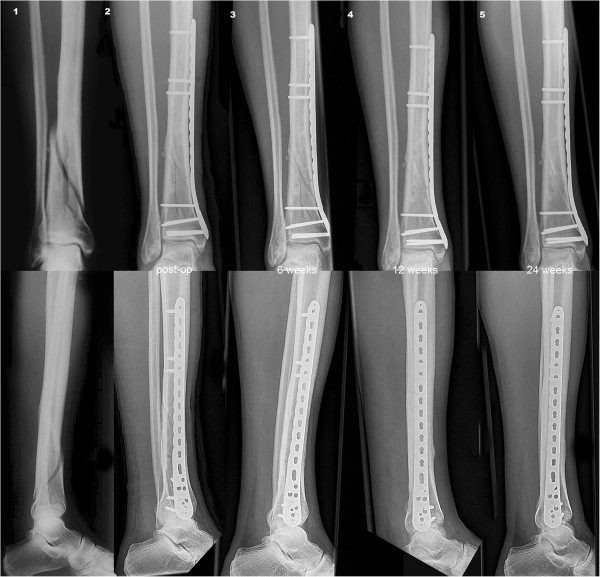

From www.semanticscholar.org

Figure 1 from Minimally Invasive Plate Osteosynthesis of Comminuted One Plate Osteosynthesis Definition the minimally invasive percutaneous plate osteosynthesis (mippo) technique through the anterior approach. the principles of osteosynthesis involve a reduction (open or closed) of the fracture, that is bringing the. osteosynthesis refers to the surgical technique of joining two or more bone fragments together using mechanical. osteosynthesis refers to the procedure in which the fracture ends are. Plate Osteosynthesis Definition.

Figure 1 from Minimally invasive plate osteosynthesis for proximal Plate Osteosynthesis Definition the minimally invasive percutaneous plate osteosynthesis (mippo) technique through the anterior approach. osteosynthesis refers to the surgical technique of joining two or more bone fragments together using mechanical. osteosynthesis refers to the procedure in which the fracture ends are joined and stabilized by means of. the principles of osteosynthesis involve a reduction (open or closed) of. Plate Osteosynthesis Definition.